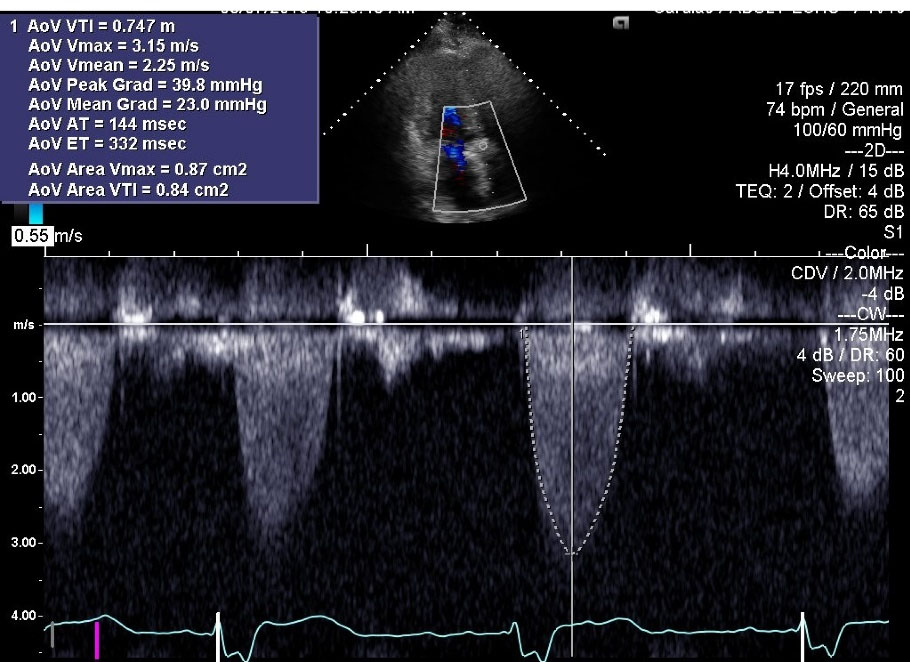

His acute decompensated heart failure was believed to be secondary to structural bio-prosthetic valve degeneration with associated critical stenosis and moderate regurgitation. Because of unstable hemodynamics, multiple comorbidities, high logistic Euro- score II of 67.0% and Society of Thoracic Surgery Risk (STS) score of 46%, the patient was deemed to be a poor surgical candidate for re-do surgical intervention. Therefore, he underwent immediate and successful TAVR with a ViV procedure with a 29 mm Medtronic Evout –R, using transfemoral approach with conscious sedation without complications. Follow up echocardiogram () one week post-procedure revealed prosthetic AV peak gradient of 64.3 mm Hg, mean gradient of 34.5 mm Hg, peak velocity of 4.01 m/s, and LVEF of 60%. The patient’s symptoms improved remarkably and he was discharged from the hospital after an extended stay of around 3 weeks. The patient had past medical history of CAD and was already on daily oral aspirin without any indication for concurrent dual antiplatelet therapy or any indication for anticoagulation. Another follow up echocardiogram at 5 months interval () revealed prosthetic AV peak gradient of 39.8 mm Hg, mean gradient of 23.0 mm Hg, and peak velocity of 3.15 m/s.

jcvtr-14-197-g003

Figure 3. Post-TAVR echocardiogram at 5 months interval; Color Doppler M-mode. Prosthetic AV peak gradient of 39.8 mm Hg, mean gradient of 23.0 mm Hg, and peak velocity of 3.15 m/s. AoV, Aortic Valve